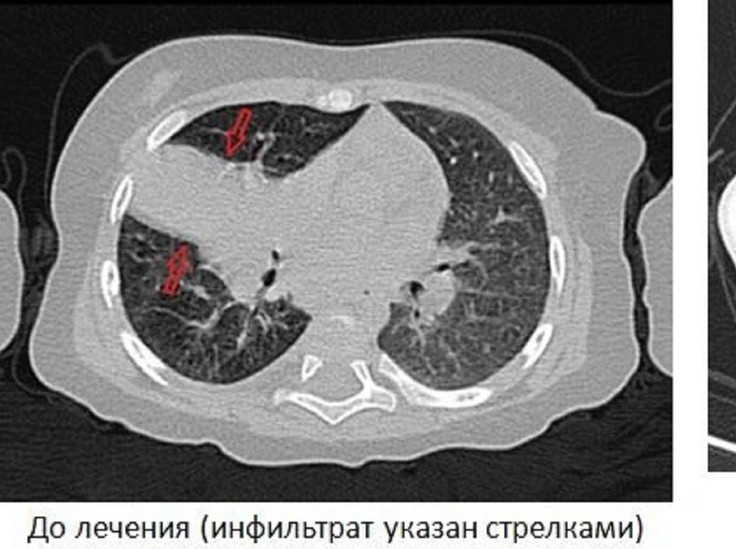

Чтобы уточнить диагноз и узнать локацию очагов заболевания, ребенку была сделана компьютерная томография легких и исследование бронхов.